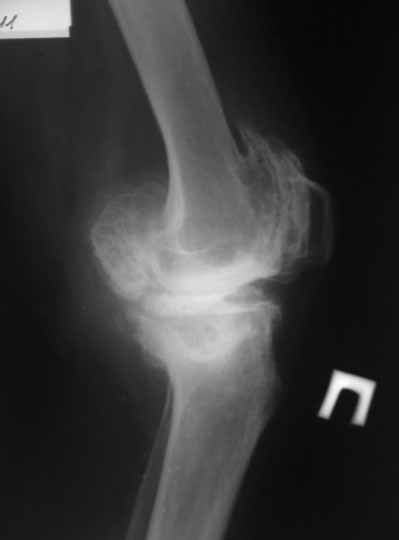

Пациентка 72 лет.Не обследовалась и не лечилась.

Работала поварихой до последнего времени.обратилась за медпомощью впервые.ходит без дополнительной опоры. Основные жалобы на ограничение движений и боли в правом коленном суставе.

Финансовые возможности ограничены.Чем можно помочь? Артродез? Протезирование?

Здравствуйте! А у вас нет ли R-гр? Для установления ст. артроза. Если же пациентка обращается первично, может стоит попробовать консервативное лечение?! НПВП, физиолечение, массаж, внутрисуставные блокады... Артродез и протезирование думаю всегда успеется.

однозначно протезирование

Больной несомненно показано эндопротезирование, однако случай не простой. Если у Вас нет достаточного опыта в проведении подобных операций, лучше направить больную в соответствующее лечебное

учреждение. По квоте.